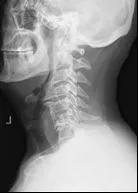

只表现为头、肩、颈和臂部疼痛和相应压痛点,X线片上没有明显的椎间隙狭窄等 “老化”改变,可发生轻度椎体间不稳定或骨质增生,颈椎生理曲度有减小或变直的改变。

颈肩部疼痛和颈椎生理曲度变直